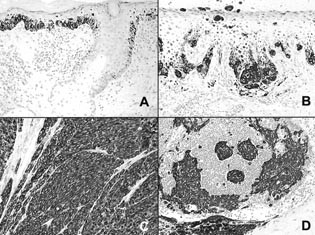

PNL2 gave a strong immunostaining of 70 to 100% of the melanocytes in all the non desmoplastic primary melanomas, irrespective of their histologic type (Figure 4). However, PNL2 did not label desmoplastic melanomas. All metastatic melanomas were positively stained by PNL2. The percentage of labeled neoplastic cells varied from case to case from 10 to 100% (mean, 45%). However, the staining was always strong, dramatically different from the weak staining of the nodal capsular nevi. The lower percentages of stained cells were most often observed in hypomelanotic lesions. A discrepancy between PNL2, HMB-45, and anti–Melan A staining was observed in two cases: PNL2 gave a strong staining of 10% of the tumors cells whereas, anti–Melan A and HMB-45 were negative.

The staining of PNL2, anti–Melan A, and HMB-45 antibodies on paraffin embedded non melanocytic tumors is detailed in Table 3. PNL2 and anti–Melan A gave a strong immunostaining of most of the neoplastic cells in clear cell sarcomas, of a few cells in angiomyolipomas (Figure 5) and of spindle cells in lymphangioleiomyomatosis. By contrast, HMB-45 immunostaining was strong in clear cell sarcomas but weak in angiomyolipomas and weak or negative in lymphangioleiomyomatosis. One case of melanotic schwannoma was strongly labeled by the three antibodies. None of the other tumors tested were found to be positive for PNL2.